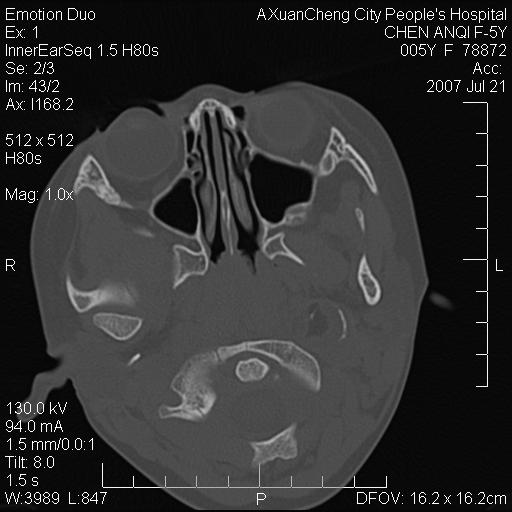

标题: PED0273:5岁,左耳流脓痛疼一周,颅底骨质破坏 [打印本页]

标题: PED0273:5岁,左耳流脓痛疼一周,颅底骨质破坏

患儿5岁,左耳流脓痛疼一周,左外耳道肉芽组织填塞 软组织窗显示病灶内结节状低密度影为气体密度

左侧中耳炎并胆脂瘤,左颞骨岩部骨质破坏并颅内感染积气。

考虑化脓性中耳乳突炎伴胆脂肪瘤形成并左颞叶感染,不除外合并嗜酸性肉芽肿.